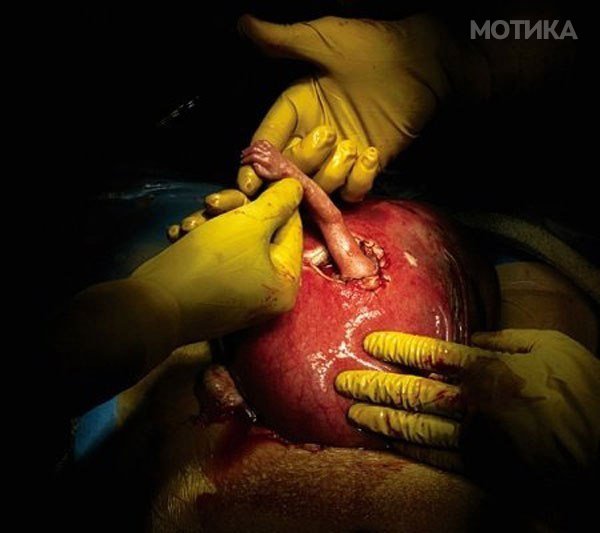

Хирурзите се нафатиле да направат една од најсложените операции: отстранување на дефект на ‘рбетот на мали бебиња уште во утробата на мајката.

Крајно ризичната операција била спроведена успешно… и одеднаш на крајот на операцијата, преку отворот на мајчината утроба, малата рака го стегнала прстот на хитутгот како да сака да му искаже благодарност!

Операцијата за отстранување на дефектот била успешна. Семјуел Александар Армас е роден на 2 декември, 1999 година.